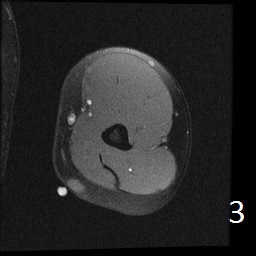

Angiolipoma is a subcutaneous benign tumor, made up of mature fat and blood vessels that often presents as multiple lesions. It sometimes arises intramuscularly. The incidence may be associated with familial heritage, close to 5% of the cases. Angiolipomas often arise in young patients, shortly before puberty, and are rarely seen in younger children or older adults. Angiolipomas often present as single or multiple subcutaneous tender to painful nodules (especially multiple ones). The pain may decrease as the lesion ages. No preference for ages or gender. Sites more commonly affected are the upper extremity and trunk, but rarely can affect head and neck region. MRI shows homogeneous and well circumscribed lesion, with intermediated signal on T1w (Fig. 1) and increased signal on T2W (Fig. 2). On fat suppress sequences the tumor may not suppress completely necause of its vascularity (Fig. 3). There is significant enhancement post contrast images (Fig. 4). On gross pathology the mass is a circumscribed, yellow-red nodular mass due high fat content and blood vessel proliferation. Microscopically, shows mature fat cells separated by branching network of small blood vessels, more prominent in subcapsular areas; there are usually associated fibrin thrombi (important sign). Adipocytes and interspersed vascular structures are seen, lined by elongated endothelial cells. These cells are irregular, and fingerlike extensions surrounded by periytes. Angiolipoma is a benign mass. It does not exhibit aggressive behavior. It rarely shows recurrence after resection. The treatment is complete surgical excision.

Fig. 1-4: Axial MRI of the arm shows a well circumscribed mass with intermediate signal on T1W (Fig. 1), and increased in T2W (Fig. 2). Fig. 3 Axial T1W FS shows a lesion and moderate intense on T1WFS post contrast (Fig. 4).